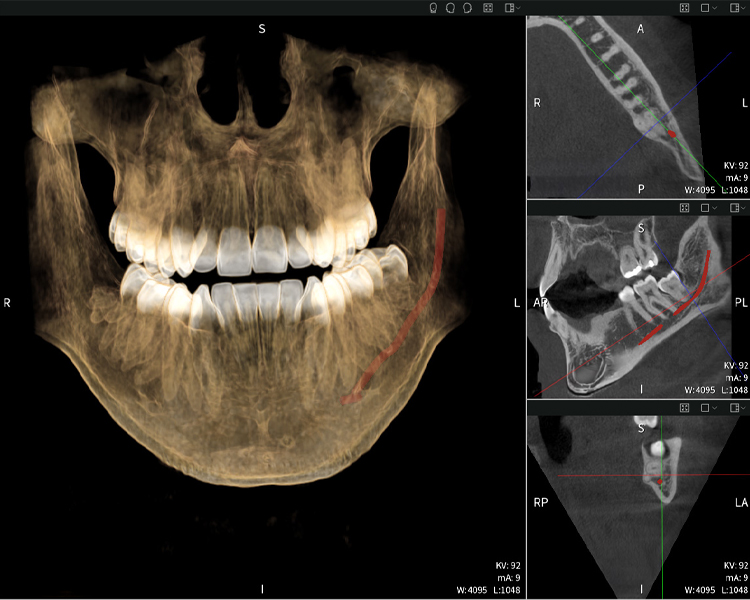

Abbildung a

- Oben links: Axiale Schnittansicht des linken Unterkiefers (Region 38) mit Darstellung des Nervus alveolaris inferior (rot) in unmittelbarer Nähe zu den Wurzeln des Zahns 38.

- Oben rechts: 3D-Rekonstruktion des gesamten Unterkiefers zur Orientierung. Der rot markierte Nervus alveolaris inferior verdeutlicht seine Lage im Kieferknochen.

- Unten links: Sagittale Ansicht des Unterkiefers (Region 38), die die enge räumliche Beziehung zwischen den Wurzeln und dem Nervenkanal verdeutlicht.

- Unten rechts: Koronale Ansicht des Unterkiefers (Region 38) entscheidend für die Beurteilung der räumlichen Lage der Wurzeln zum Nerven.